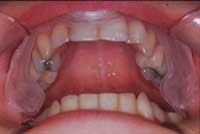

La maggior pressione da un lato farà defluire il liquido su quello opposto innescando un meccanismo di feedback (Foto 3) che tenderà in pochi minuti alla normalizzazione dei muscoli interessati. In pratica i due cuscinetti ricreano quell’appoggio indispensabile alla normalizzazione del sistema neuromuscolare. Il Paziente, da solo, utilizzando le sue funzioni riflesse, in modo involontario, a poco a poco si posiziona in una zona di equilibrio. Queste placche, davvero geniali, avevano il difetto di essere molto indaginose da realizzare. Ora, grazie al sistema Aqualizer®, tutto ciò è superato, in quanto sono state realizzate delle pseudoplacche preformate in tre misure che si adattano praticamente a tutte le arcate dentarie, a patto naturalmente che siano presenti elementi dentali sufficienti. (Foto 1 e 2)